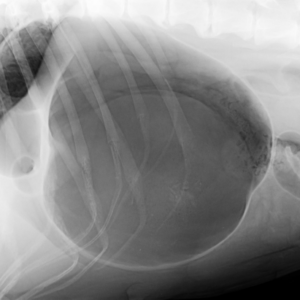

Strašák jménem TORZE ŽALUDKU

V minulém čísle jsme vám přinesli příběh se šťastným koncem, kdy fenka německého ovčáka přežila torzi žaludku. Na toto téma nám přišlo větší množství dotazů a tak nyní přinášíme téma uceleně zpracované MVDr. Milanem Štouračem. Syndrom dilatace a torze žaludku…